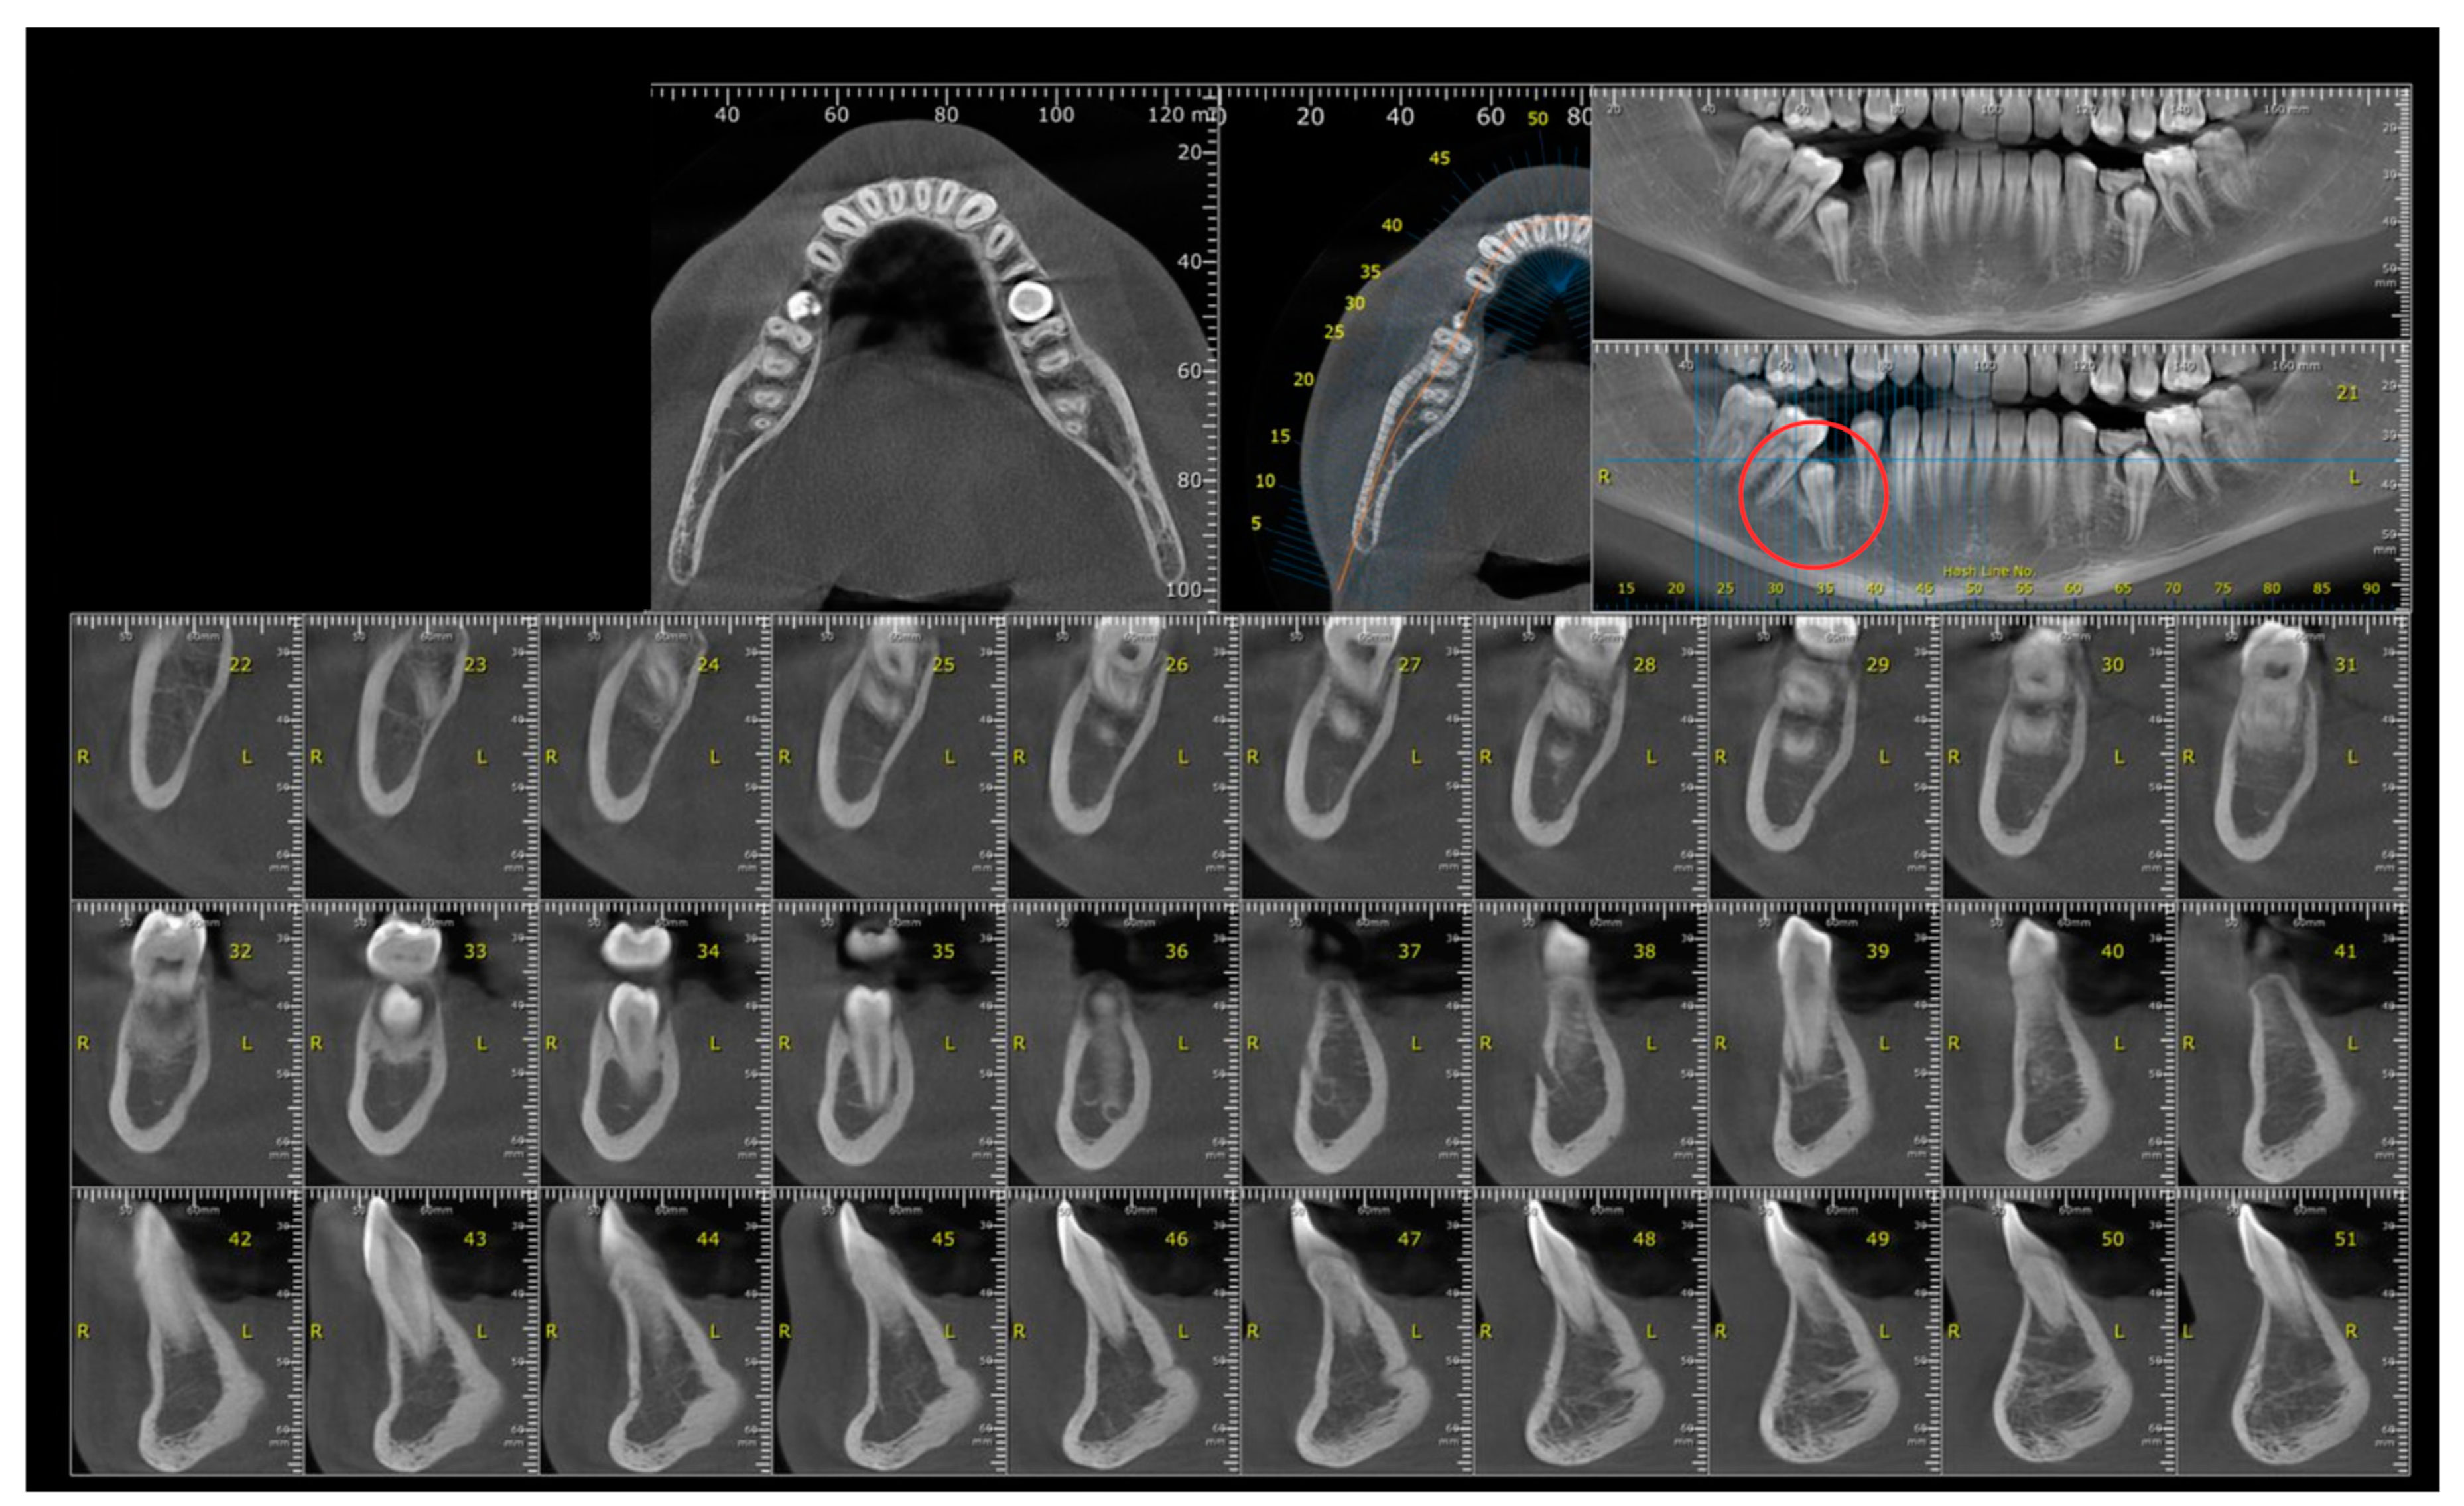

2. Case Report

2.1. Examination, Diagnostics, and Initial Therapeutic Management